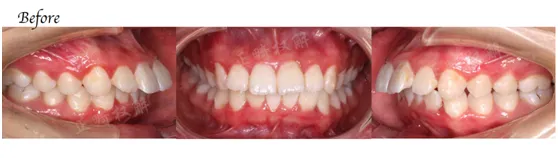

3、不拔牙病例十五例具体病例详细分析(病例从简单到复杂)(理论)

7、十五例拔牙病例分步详解(理论)